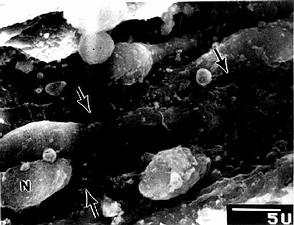

脾血窦(splenic sinus):是一种静脉性血窦,宽约12~40μm,形态不规则,相互连接成网。窦壁由一层长杆状的内皮细胞平行排列而构成。内皮细胞之间常见许多0.2~0.5μm宽的间隙,脾索内的血细胞可经此穿越进入血窦(图9-21,9-22)。内皮外有不完整的基膜及环行网状纤维围绕,故血窦壁如同一种多孔隙的栏栅状结构。在血窦的横切面上,可见杆状内皮细胞沿血窦壁呈点状排列,较粗大的内皮细胞断面中可见有细胞核,并突入管腔(图9-19)。血窦外侧有较多的巨噬细胞,其突起可通过内皮间隙伸向窦腔。

图9-22 大鼠脾血窦扫描电镜像

N内皮细胞核,↑内皮质间隙